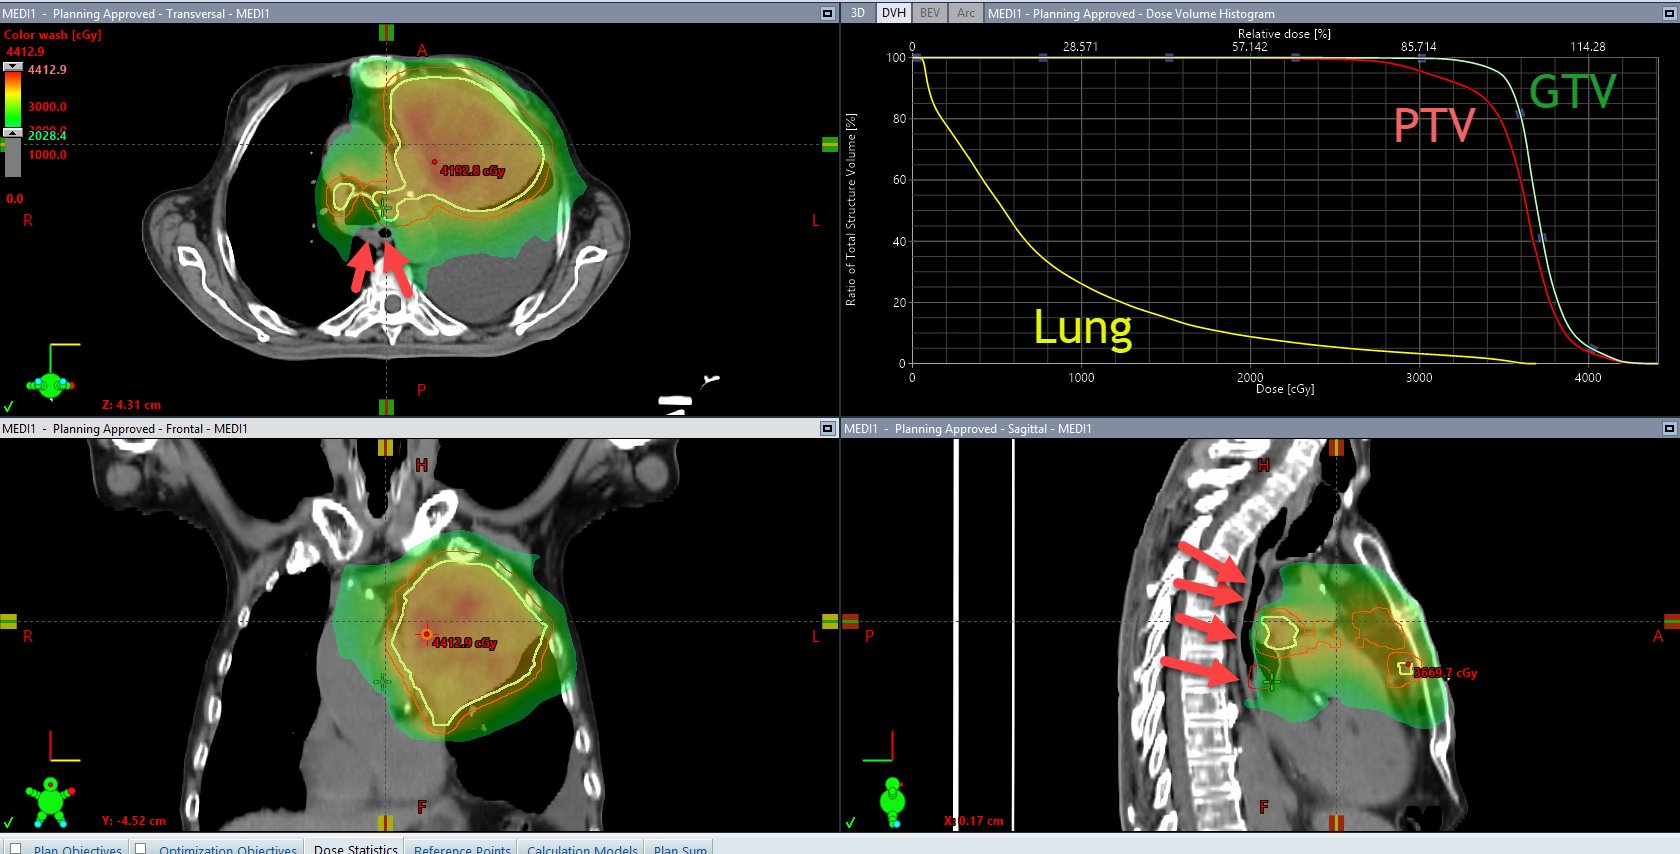

David Palma, Radiation Oncologist at London Health Sciences Centre (LHSC), shared a post on X:

“Here’s a nice RT plan from Chris Goodman’s PREVENT RCT.

Standard arm: 20 Gy/5 or 30 Gy/10

Experimental arm: 35 Gy/5 with allowance for a hot spot (in this case 44 Gy/5)

Arrows show esophageal sparing to ~ 20 Gy/5, PTV compromised in that area.”